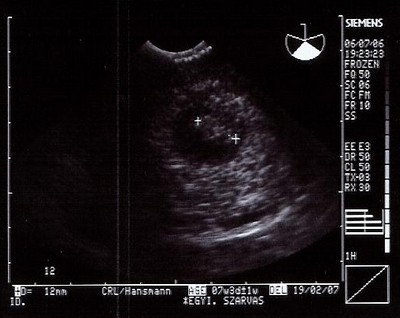

Tegnap este voltunk dokibácsinál, és láttuk a kis Mákszemünket. bejött a férjem is és együtt néztük ellágyulva, hogyan ver a pici szíve. Olyan jó volt, Olyan boldog vagyok!:D :D :D :D :D

12mm-es a baba, és teljesen egészséges. Itt egy kép róla. Aranyos volt a doki, nem is mertem kérni, magától adta a képet. :D

Amúgy volt jobb kép is a babáról, amikor egész baba alakja volt, látszott a kis buksija, meg a pici végtagbimbók is.

Még mozgott is. :D A doki azt mondta, hogy ezek még elemi mozgások, de azért megnehezíti a dolgát, hogy befogja az UH-val. :)

A kis huncut el akart bújni. :wink: